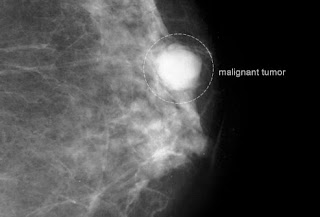

1- سرطان الثدي:

الكشف المبكر عن وجود سرطان الثدي يحسن كثيرا فرص النجاة من هذا المرض.حيث يُكتشف الورم صغير الحجم قبل أن يظهر فيكون من السهل ازالته جراحيا.كما ان تلك الاورام الصغيرة تقل فرصة انتشارها للعقد الليمفاوية المجاورة او الاعضاء مثل الرئتين و المخ.

ان كانت المرأة ما بين ال20 - 30 عاما ولا يوجد لديها عوامل مساعدة للاصابة بهذا المرض,فيجب أن تواظب علي اجراء فحص دوري من قِبل متخصصين كل 3 سنوات.

2- فحص الثدي بالأشعة:

هناك توصيات شديدة باجراء فحص الأشعة الروتيني هذا.فالجمعية الأمريكية للسرطان تنصح باجرائه سنويا للمرأة المهددة بخطر الاصابة به بداية من سن الأربعين , ورأي آخر لفريق الخدمات الوقائية بالولايات المتحدة باجرائه روتينيا كل سنتين من 50 وحتي 74 سنة .

و ترجع أهمية هذا الفحص الي أن تلك الجرعات الصغيرة من الأشعة التي تستخدم فيه كفيلة بالكشف عن ورم صغير قبل الاحساس بوجود كتلته ب 3 سنوات ! ومع ذلك لا يكفي هذا الفحص للاطمئنان لعدم وجود ورم